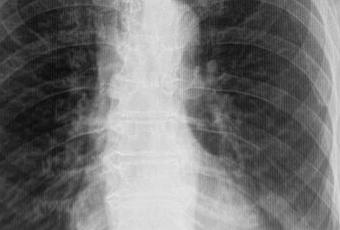

-Hilios pulmonares, con adecuada densidad. Existiendo en hilio pulmonar izquierdo, la presencia de imagen redondeada, regular, bien definida que mide 7 × 5 mm.

-Campos pulmonares, con opacificación reticular difusa, a nivel de hilio pulmonar izquierdo, con presencia de imagen redondeada, regular, bien definida que mide 7 × 5 mm.

EN EL PRESENTE ESTUDIO RADIOGRÁFICO, CON DATOS DE NEUMOPATÍA CRÓNICA INTERSTICIAL.

PULMÓN IZQUIERDO, EN TOPOGRAFÍA BILIAR, CON PRESENCIA DE IMAGEN SUGERENTE DE GANGLIO VS NÓDULO O GRANULOMA CALCIFICADO.